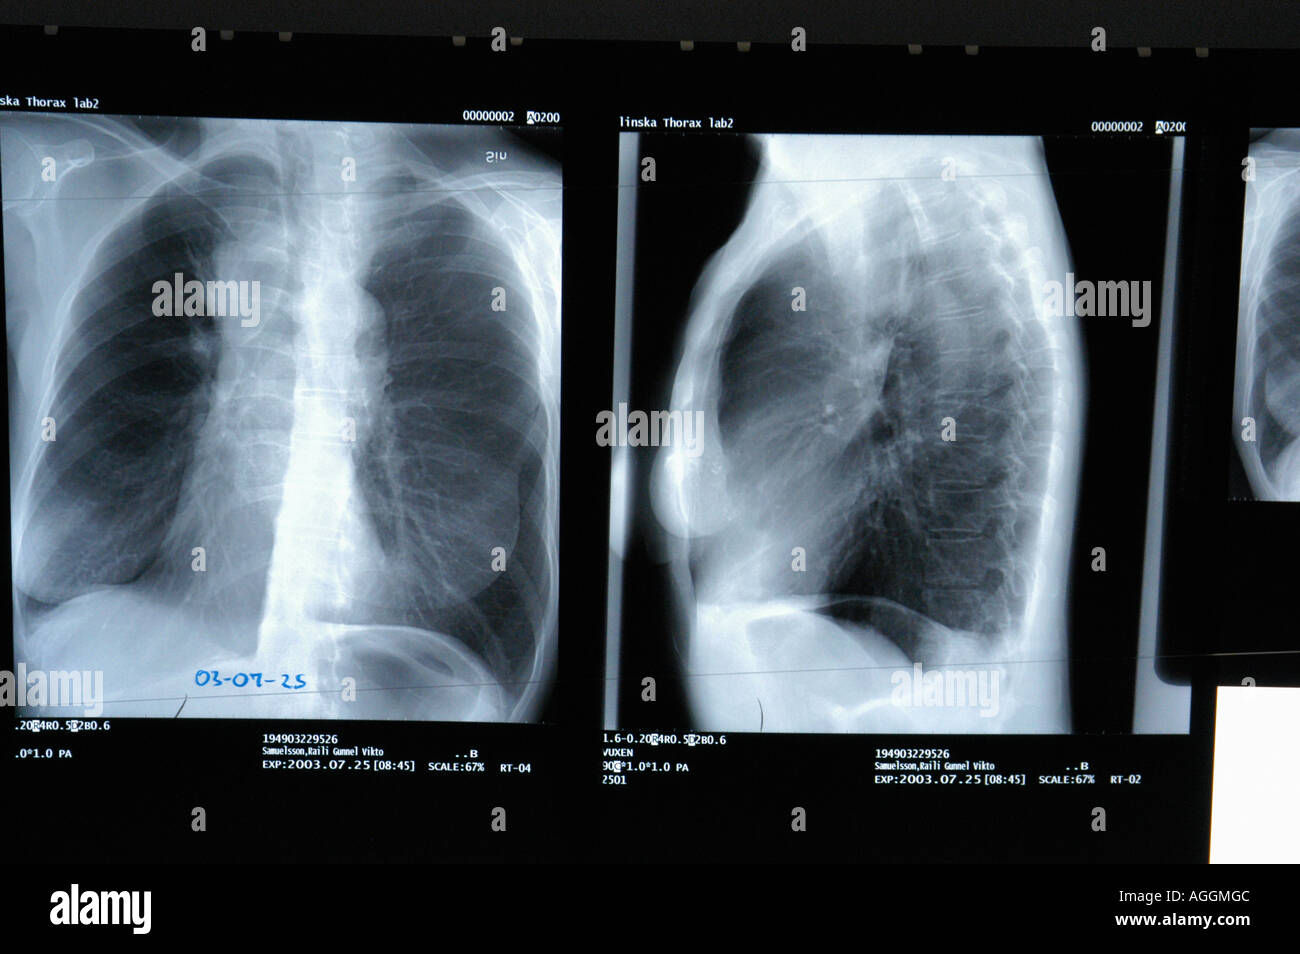

Röntgenbilder sind eine schnelle und relativ kostengünstige Methode, um einen ersten Blick in die Lunge zu werfen. Sie sind oft der erste Schritt, wenn jemand Symptome wie anhaltenden Husten, Kurzatmigkeit oder Brustschmerzen hat. Denk dir die Röntgenaufnahme als eine Art Schwarz-Weiß-Foto deiner Lunge. Dichte Strukturen, wie Knochen, erscheinen weiß, während Lufträume, wie die gesunde Lunge, schwarz erscheinen. Veränderungen in diesem Muster können auf Probleme hinweisen.

Obwohl Röntgenbilder nicht so detailliert wie andere bildgebende Verfahren (z.B. CT-Scans) sind, können sie verdächtige Bereiche identifizieren, die weitere Untersuchungen erfordern. Stell dir vor, du suchst nach einem versteckten Gegenstand in einem leicht abgedunkelten Raum. Das Röntgenbild gibt dir einen ersten Hinweis, wo du genauer suchen musst.

Wie ein Röntgenbild interpretiert wird

Die Interpretation eines Röntgenbildes ist Aufgabe eines Radiologen, eines Arztes, der auf die Interpretation von medizinischen Bildern spezialisiert ist. Der Radiologe betrachtet das Bild sorgfältig und achtet auf die oben genannten Anzeichen. Er berücksichtigt auch die Krankengeschichte des Patienten und andere relevante Informationen, um eine Diagnose zu stellen.

Es ist wichtig zu verstehen, dass ein Röntgenbild keine definitive Diagnose liefert. Es kann lediglich verdächtige Bereiche identifizieren, die weitere Untersuchungen erfordern. Wenn auf einem Röntgenbild etwas Verdächtiges gefunden wird, werden in der Regel weitere bildgebende Verfahren, wie ein CT-Scan oder eine MRT, durchgeführt, um die Diagnose zu bestätigen.